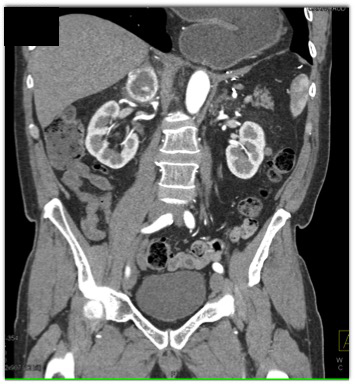

The best diagnosis for this incidental adrenal mass in a 65 yr. old male is?

CTisus Quiz   CTisus Quiz

adrenal adenoma

metastatic renal cell carcinoma

pheochromocytoma

adrenal hematoma